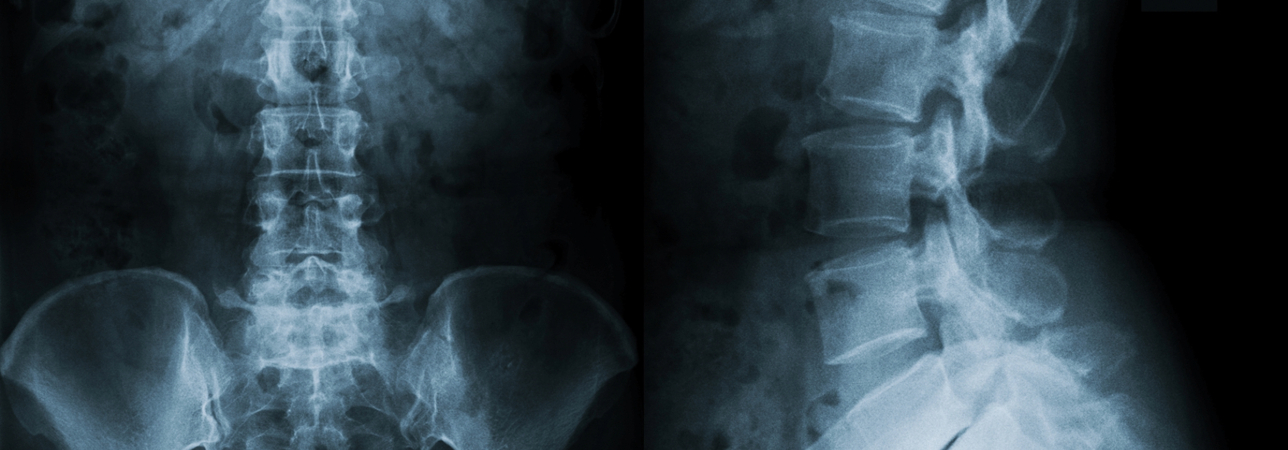

In der Clinica Ars Medica befindet sich ein spezialisiertes Zentrum mit dem Ziel, die Lebensqualität von Patienten mit Schmerzen im Zusammenhang mit Wirbelsäulenerkrankungen zu verbessern. Dr. med. Maurizio Pintucci, Neurochirurg-Wirbelsäulenchirurg.

Was ist das Ars Medica Centro Colonna Vertebrale?

"Es handelt sich um eine hochqualifizierte Einrichtung, die über einen Hauptsitz im renommierten Ambrosart-Komplex in Manno und einen zweiten Sitz in Muralto-Locarno innerhalb der Tertianum Residenza Al Parco verfügt. Das Zentrum vereint eine Reihe von Wirbelsäulenspezialisten, die in Synergie zusammenarbeiten, um Patienten mit Schmerzen im Zusammenhang mit Wirbelsäulenerkrankungen eine hochmoderne, multidisziplinäre und somit umfassende Betreuung zu bieten und ihnen die Möglichkeit zu bieten, alle erforderlichen medizinischen Untersuchungen, diagnostischen Tests und Behandlungen durchzuführen. Kurz gesagt, das Zentrum verfügt über alle Kompetenzen, dank derer die klinische Anamnese von einer schnellen diagnostischen Ergänzung und einem individuellen Therapievorschlag auf der Suche nach dem besten Therapie- und Rehabilitationsweg begleitet wird".